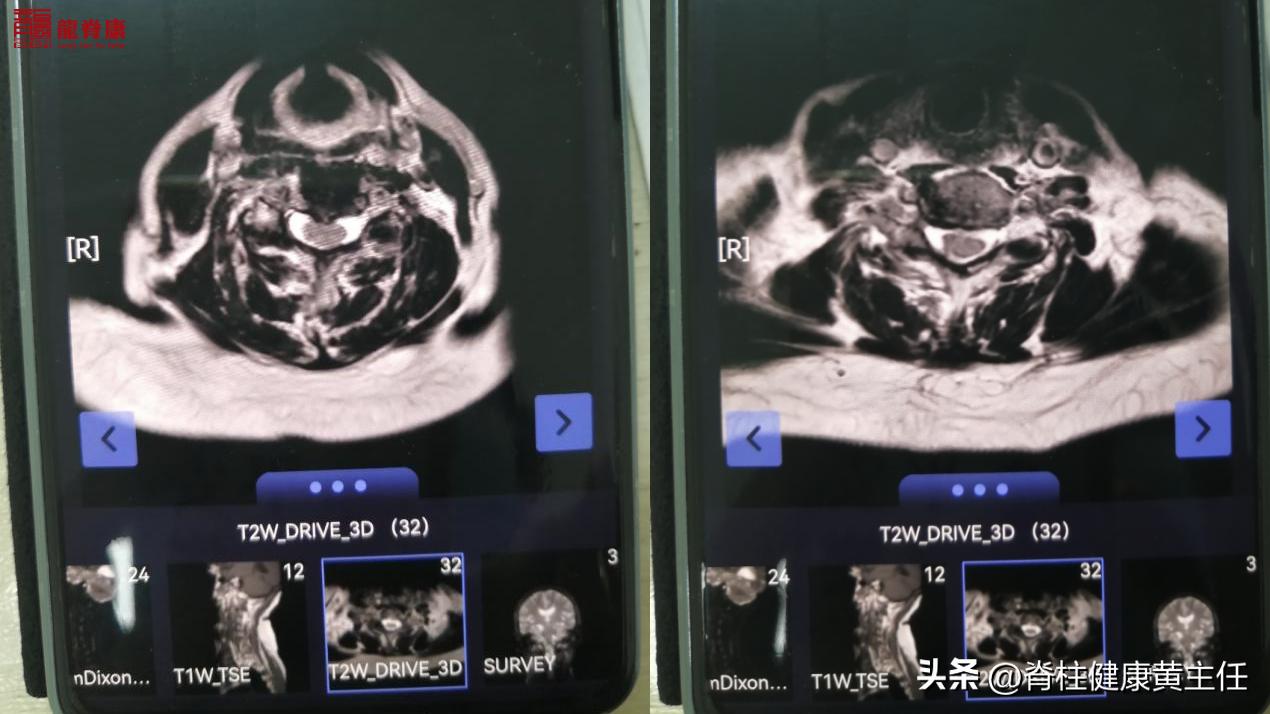

外院颈椎MR专科描述示:

颈椎曲度存在,顺列尚齐。颈椎椎体边缘轻度骨质增生,颈椎椎体及附件信号无异常。颈椎间盘信号在T2W1上普遍减低。颈2/3-6/7椎间盘不同程度向后中央突出,硬膜囊受压,其中颈4/5椎间盘突出较前加,脊髓轻度受压,双侧椎间孔无变窄,神经根无受压。后纵带及黄韧带无增厚,椎管前后无狭窄。脊膜无增厚及无异常信号影,脊髓形态、信号未见异常。椎管内未见异常信号影。

但由于MRI检查显示颈4/5椎间盘突出较前加重,脊髓受压;并且患者年纪较大82周岁,有存在明显的骨质疏松;因此在手法复位上存在安全风险,不适宜做有闪动力的手法正骨复位。但可以进行缓慢的、轻力度(无闪动力)的颈椎关节松动术,解除颈椎上段小关节错位卡压的问题;配合理疗、热疗等,促进颈部血液循环,以缓解头晕不适。